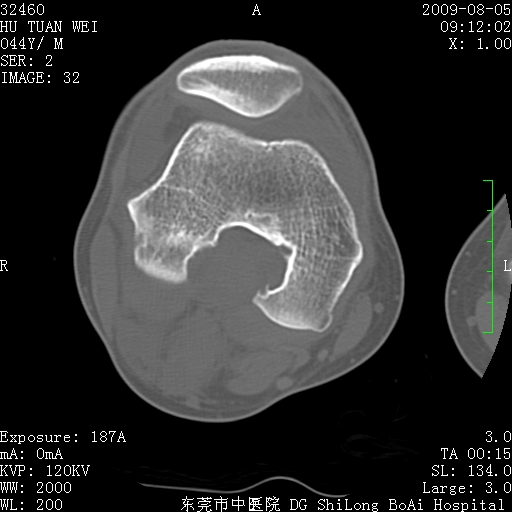

标题: CT21940:膝关节(有病理)

中年男性,膝韧带损伤术前检查!其他病史不清粗,不是我接手病人、且出院了!

1、股骨下段囊状膨胀性病变,边缘硬化明显,内多个残留骨棘呈多房型改变,囊腔密度较高无钙化,膝关节滑膜囊增厚,密度增高,关节腔少量积液。考虑:邻关节囊肿、退变性囊肿(软骨下囊肿)、着色性绒毛结节性滑膜炎、abc、骨巨、良性纤维组织细胞瘤等鉴。虽然年龄偏大,部位于骨端,但有外伤史,本人还是倾向于动脉瘤样骨囊肿(abc)可能性大。邻关节囊肿及软骨下囊肿次之考虑。

2、胫骨髁间棘撕脱骨折,交叉韧带损伤可能;

3、关节退行性改变。

病理结果:色素沉着绒毛结节性滑膜炎

感谢反馈病理结果!本病为慢性关节病变。以关节滑膜高度增生、绒毛结节形成伴含铁血黄素趁着为特点。病因:有炎症、肿瘤、外伤关节出血、代谢障碍、变态反应及感染等学说。增强扫描呈关节腔内单个或多个强化的软组织结节影或滑膜不规则增厚伴关节积液为本病的特征性表现。